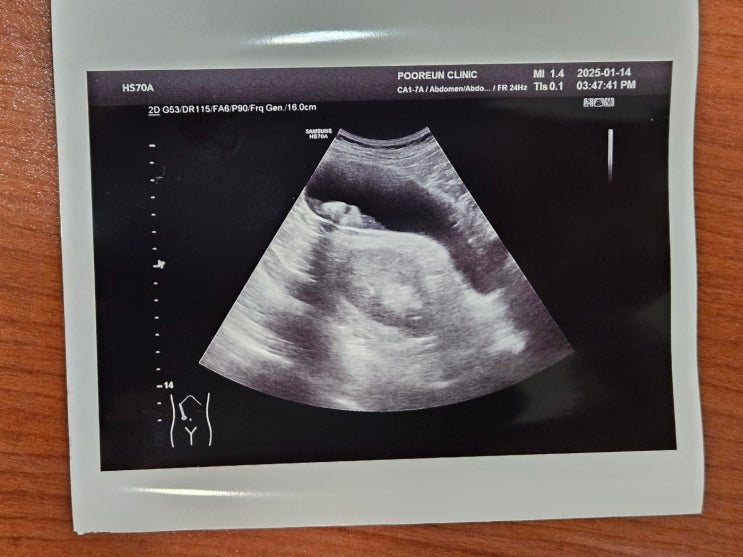

2025.1.14 배가 터질(?) 것 같다며 온 환자

74세 된 노인. 체했다며 말그대로 배가 터질것 같다고 했다. 하루전에 소염제랑 이것저것 드신 모양인데 열...